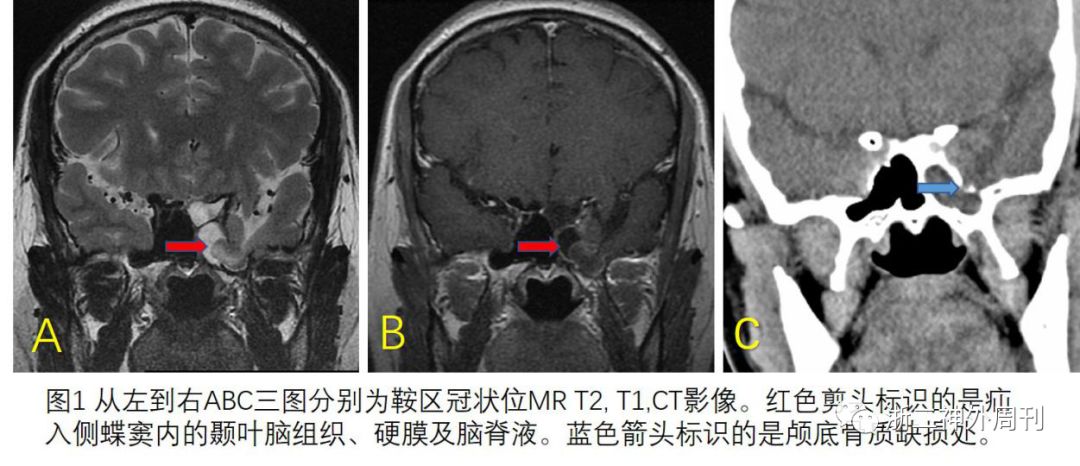

入院后完善各项检查,鼻腔流出液行常规检查证实为脑脊液。腰穿压力120mmH2O,脑脊液检查:蛋白 0.37g/l,糖 3.5mmol/l,其余各项指标也未见异常。 内分泌常规检查正常。头颅MRI检查示:左侧颞叶部分脑组织及脑脊液疝入左侧蝶窦内;空泡蝶鞍(图1A,B)。冠状CT提示左颅中窝底局部缺损(图1C)。

结合患者病史、临床表现和各项检查结果,考虑为:Sternberg管未闭脑膜脑膨出致自发性脑脊液鼻漏。